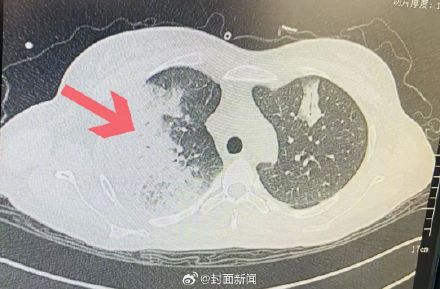

8月初,37岁的孕妇小梅出现不明原因的发烧,还伴有寒战、咳嗽、白痰、眩晕等症状,肺部感染严重,已经出现了大面积的“白肺”。医院“抽丝剥茧”搜寻感染源后,发现“罪魁祸首”竟是一只手养鹦鹉,让患者感染了鹦鹉热。8月20日,记者从医院获悉小梅已经顺利出院。